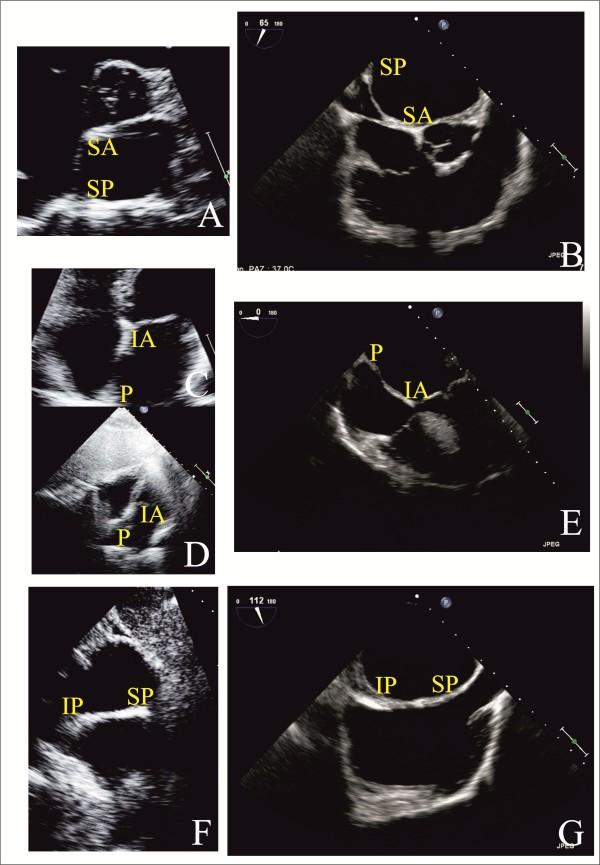

Aortic stenosis and mitral regurgitation, patent foramen ovale, interatrial septal defect, atrial fibrillation and perivalvular leak, are now amenable to percutaneous treatment. These percutaneous procedures require the use of Transthoracic (TTE), Transesophageal (TEE) and/or Intracardiac echocardiography (ICE). This paper provides an overview of the different percutaneous interventions, trying to provide a systematic and comprehensive approach for selection, guidance and follow-up of patients undergoing these procedures, illustrating the key role of 2D echocardiography.

主动脉瓣狭窄、二尖瓣反流、卵圆孔未闭、房间隔缺损、心房颤动及瓣周漏,目前均适合经皮治疗。这些经皮手术需要使用经胸超声心动图(TTE)、经食管超声心动图(TEE)和/或心内超声心动图(ICE)。本文概述了不同的经皮介入治疗,试图为接受这些手术的患者提供一种系统、全面的选择、指导及随访方法,并阐述二维超声心动图的关键作用。